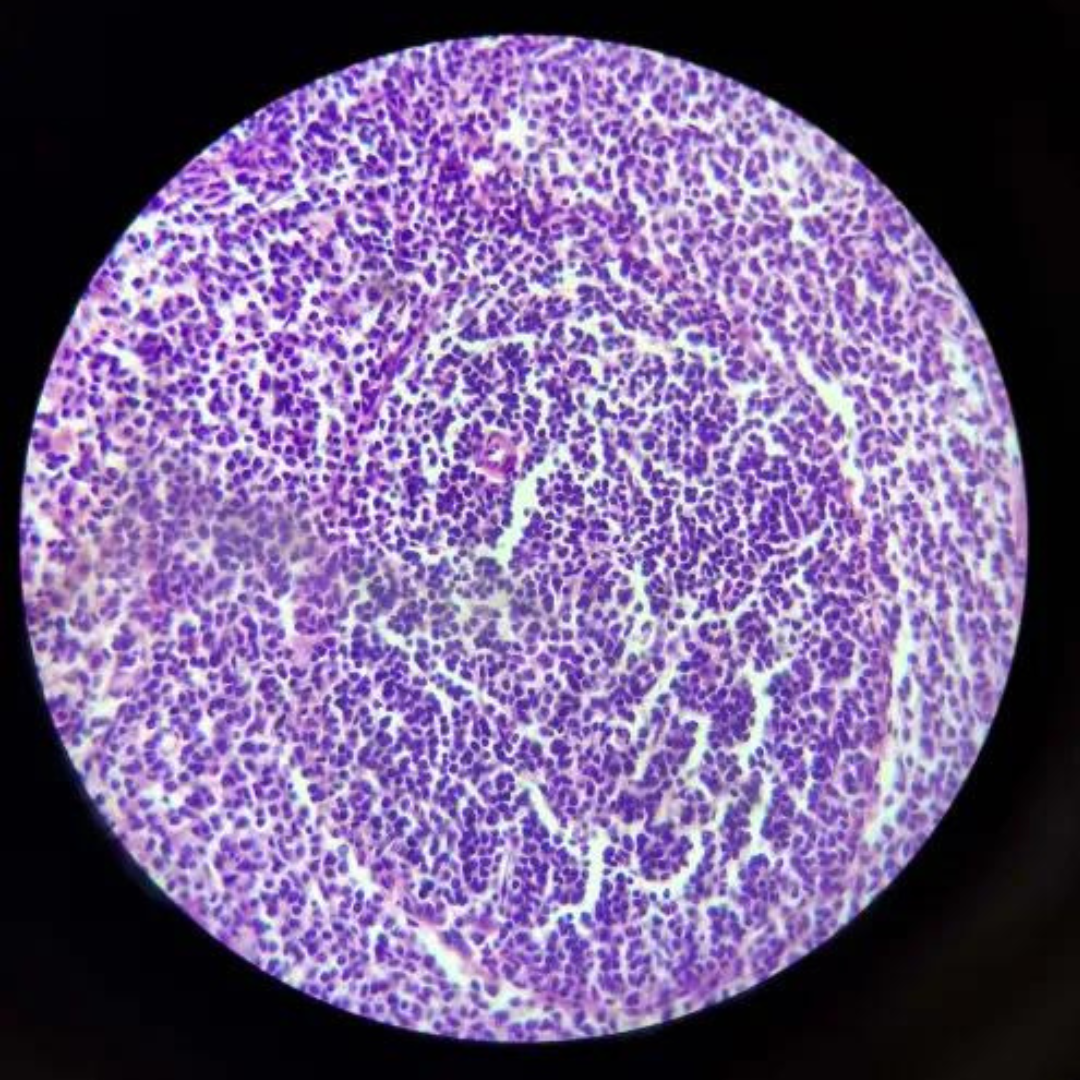

Lymph Node

11

New cards

Lymph Node

12

New cards

Lymph Node

13

New cards

Lymph Node

14

New cards

Lymph Node

15

New cards

Lymph Node